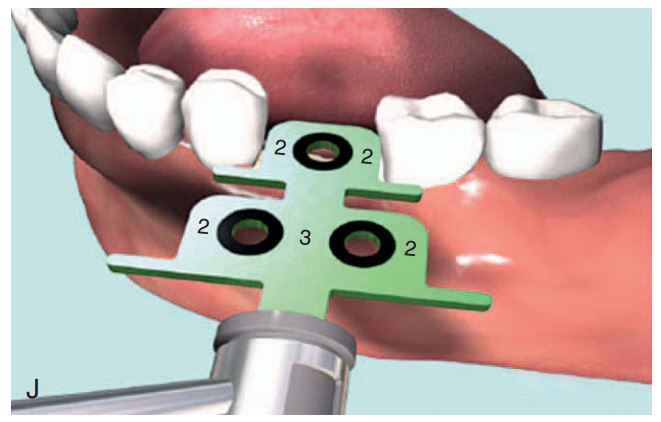

Giúp xác định đúng vị trí đặt Implant và lựa chọn đường kính Implant tối ưu nhất (H2.18). Bộ hướng dẫn ITT gồm có:

– Tấm Titan, giúp hướng dẫn đường kính và vị trí của 1 – 2 Implant.

– Cán của tấm Titan, giúp cầm nắm và đặt tấm Titan vào trong miệng 1 cách an toàn.